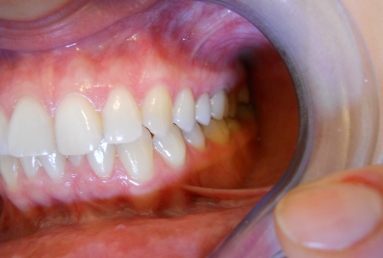

Full ceramic crowns on upper second premolar and first upper molar